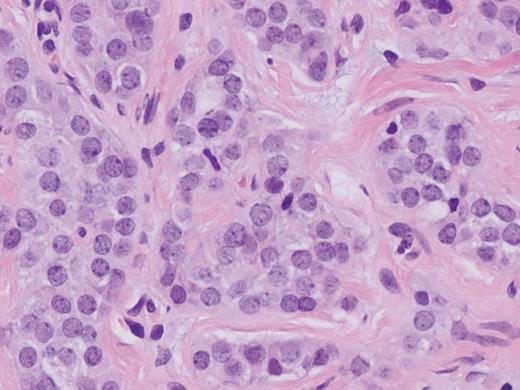

A 58-year-old Caucasian female presented with episodic right upper quadrant pain for the past 2 weeks. The pain was associated with multiple episodes of nausea, vomiting and diarrhea. She denied any jaundice, weight loss, hematochezia or melena. Physical examination revealed a soft abdomen without a palpable mass. She had tenderness in the right upper quadrant of the abdomen and Murphy's sign was present. The white blood cell count was 18.8K/µl, hematocrit 41.0%, bilirubin 0.20 mg/dl, lipase 101 U/l, alkaline phosphatase 70 U/l, alanine aminotransferase 28 U/l and aspartate aminotransferase 30 U/l. Computed tomography of the abdomen showed an enlarged fatty liver, mildly prominent gallbladder and inflammatory changes and edema at the root of the mesentery. Abdominal ultrasound revealed gallbladder sludge and wall thickness measuring 2 mm. The patient underwent laparoscopic cholecystectomy. Pathology report revealed mild chronic cholecystitis with foci of cholesterolosis and a small 2 mm carcinoid tumor at the cystic duct margin extending into the gallbladder mucosa. Histologically, the tumor demonstrated uniform eosinophilic neoplastic cells with oval nucleus (Fig. 1) and was positive for chromogranin and synaptophysin neuroendocrine markers (Figs 2 and 3).

Carcinoid tumor at the cystic duct margin (H&E, magnification ×40).